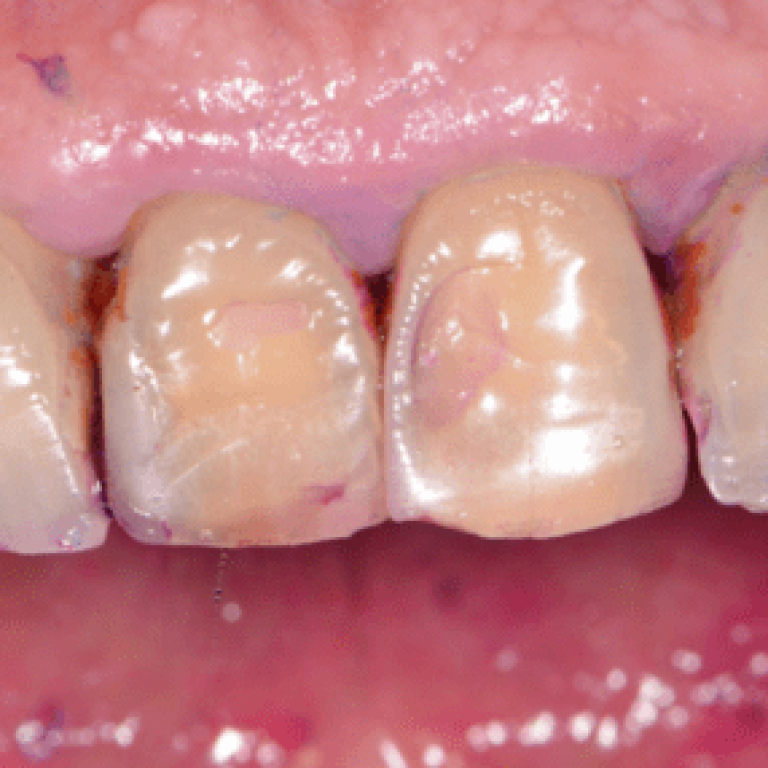

Una corretta igiene orale passa prima di tutto dalla consapevolezza della veridicità delle informazioni che riceviamo. Scopriamo allora …